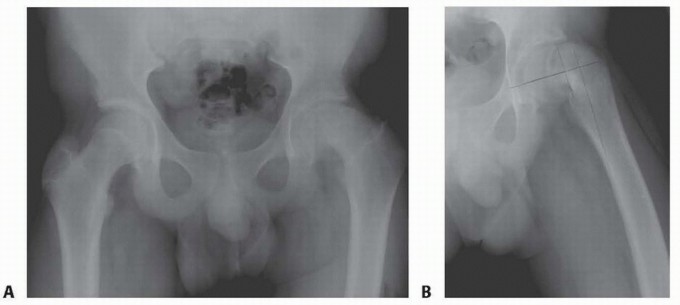

Flexion Intertrochanteric Osteotomy for Severe Slipped Capital Femoral Epiphysis DEFINITION Pistol grip defor…